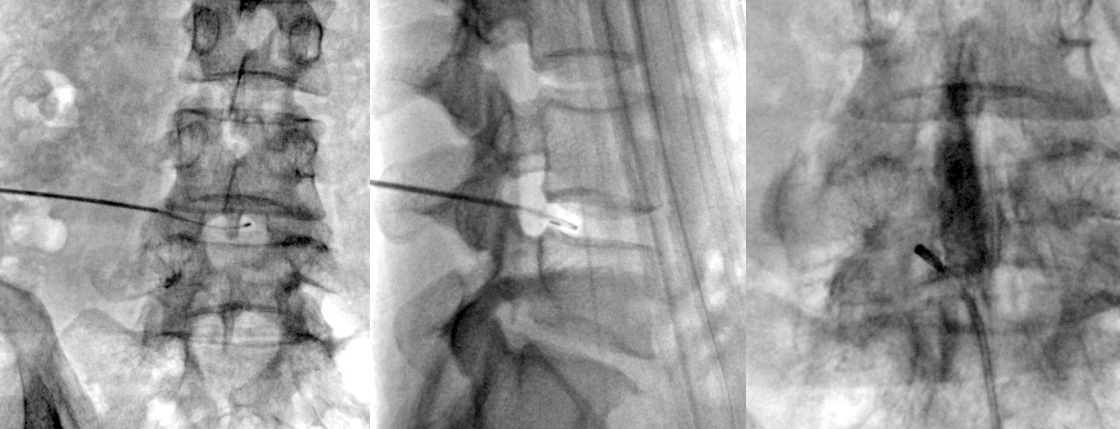

고주파수핵성형술은 디스크가 완전히 파열되지 않거나 아직 나이가 젊고 상태가 수술할 정도로 심각하지 않은 경우에 적용됩니다.

직경 2mm 이내의 가느다란 주사바늘을 문제가 생긴 디스크에 병변에 고주파에너지를 쏘아 척추신경을 압박하는

디스크내의 분자를 분해하고 녹인 후 수축 응고시키는 치료 방법입니다.

전신마취가 아닌 부분 마취 후 간단한 시술방법으로 조기 보행이 가능하고, 심하게 무너진 척추골의 높이를 교정할 수 있습니다.

회복기간도 짧아 많이 적용되는 치료 방법입니다.